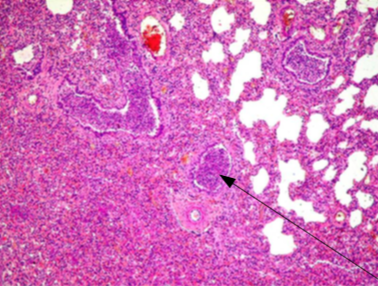

Identify:

Describe Macro appearence

and

this lesion is a complication of?

Bronchopneumonia

macro: multifocal changes. Inflammations are yellow.

-Usually complication of bronchitis